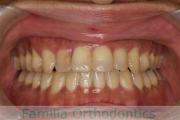

No.22V-409

- 叢生

- 16歳

- 女性

- 上:

- 44

- 下:

- 8|58

- 主な使用装置:

- FEA

- 治療にかかった費用:

- 86万円

八重歯を治したいということで来院されました。下あごの左ずれのある上顎前突(出っ歯)・叢生(でこぼこ)でしたので、上は左右から、下はで左のみ小臼歯を抜歯して、歯科矯正用アンカースクリューとマルチブラケット法にて治療を行いました。2年強、30回程度の通院が必要でした。

上下とも前歯の叢生(でこぼこ、凹凸、ガタガタ)があるため、保定を怠ると後戻りのリスクがあります。